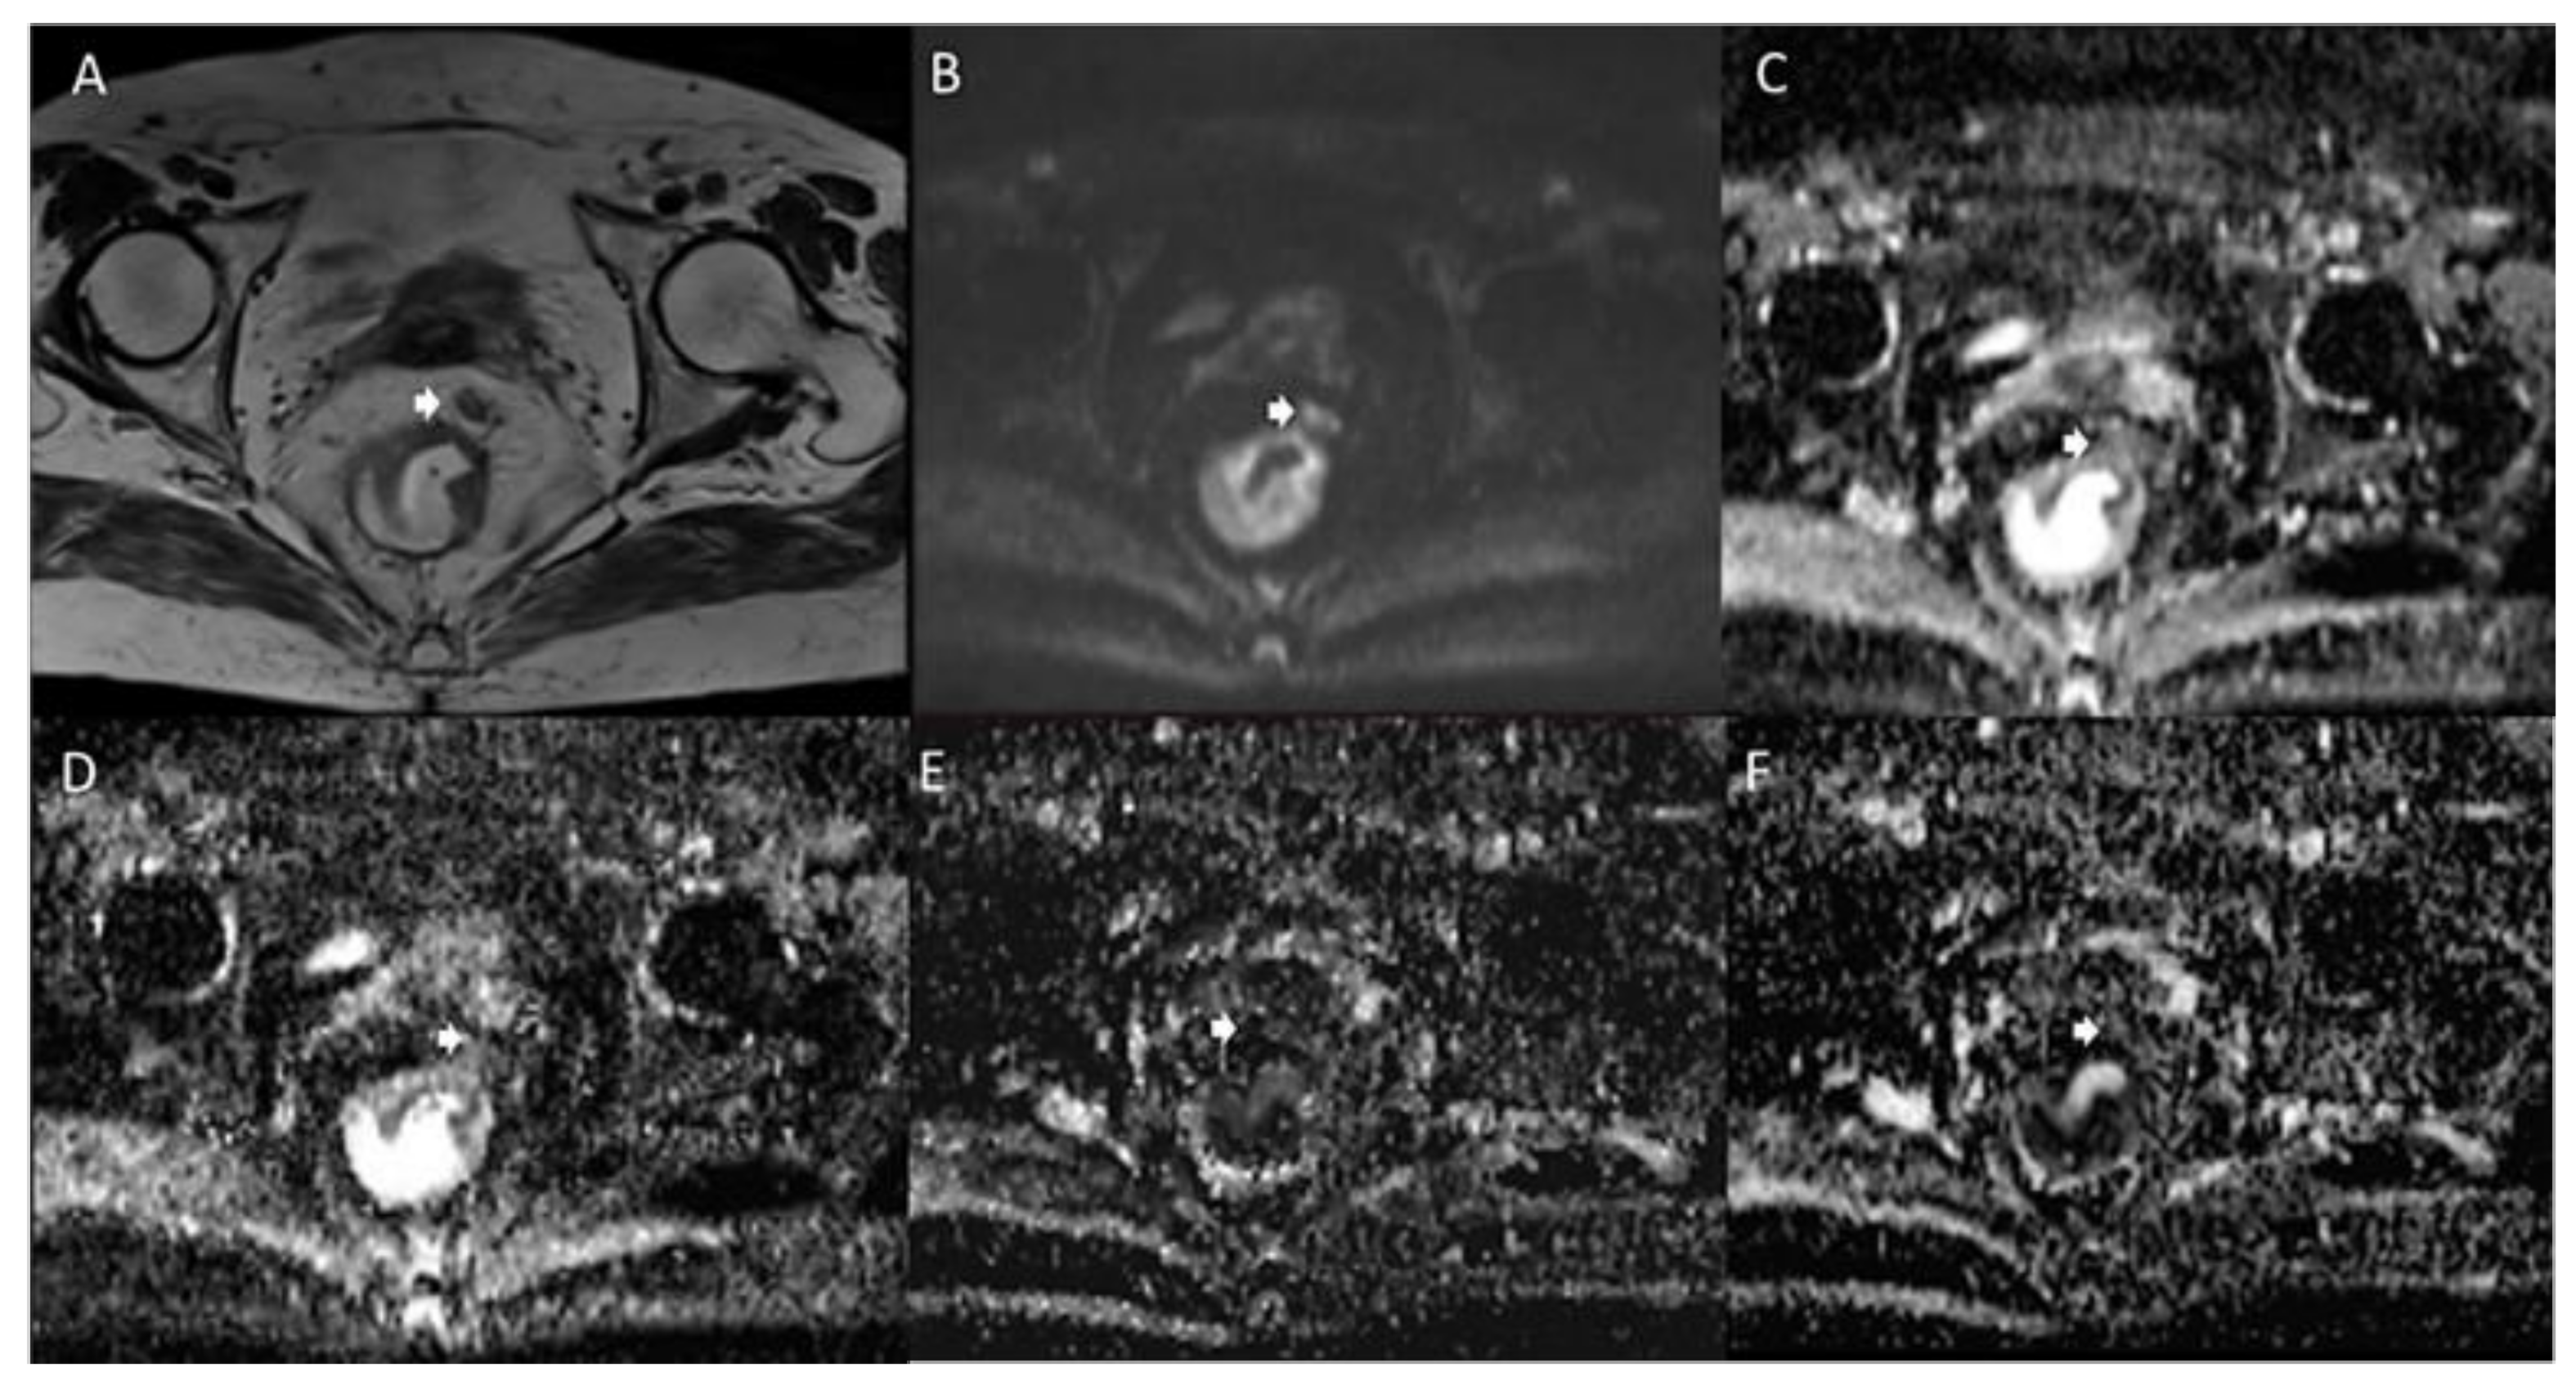

- Heijnen, L.A.; Lambregts, D.M.J.; Mondal, D.; Martens, M.H.; Riedl, R.G.; Beets, G.L.; Beets-Tan, R.G.H. Diffusion-Weighted MR Imaging in Primary Rectal Cancer Staging Demonstrates but Does Not Characterise Lymph Nodes. Eur. Radiol. 2013, 23, 3354–3360. [Google Scholar] [CrossRef]

- Lambregts, D.M.J.; Maas, M.; Riedl, R.G.; Bakers, F.C.H.; Verwoerd, J.L.; Kessels, A.G.H.; Lammering, G.; Boetes, C.; Beets, G.L.; Beets-Tan, R.G.H. Value of ADC Measurements for Nodal Staging after Chemoradiation in Locally Advanced Rectal Cancer—a per Lesion Validation Study. Eur. Radiol. 2011, 21, 265–273. [Google Scholar] [CrossRef] [Green Version]

- Mir, N.; Sohaib, S.; Collins, D.; Koh, D. TECHNICAL ARTICLE: Fusion of High B-value Diffusion-weighted and T2-weighted MR Images Improves Identification of Lymph Nodes in the Pelvis. J. Med. Imaging Radiat. Oncol. 2010, 54, 358–364. [Google Scholar] [CrossRef]

- Mizukami, Y.; Ueda, S.; Mizumoto, A.; Sasada, T.; Okumura, R.; Kohno, S.; Takabayashi, A. Diffusion-Weighted Magnetic Resonance Imaging for Detecting Lymph Node Metastasis of Rectal Cancer. World J. Surg. 2011, 35, 895–899. [Google Scholar] [CrossRef]

- Van Heeswijk, M.M.; Lambregts, D.M.J.; Palm, W.M.; Hendriks, B.; Maas, M.; Beets, G.; Beets-Tan, R.G.H. DWI for Assessment of Rectal Cancer Nodes After Chemoradiotherapy: Is the Absence of Nodes at DWI Proof of a Negative Nodal Status? Am. J. Roentgenol. 2016, 208, W79–W84. [Google Scholar] [CrossRef]